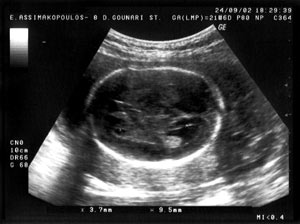

διατομή και πάλι με υπερηχογενή όρια προς τα επάνω και προς τα κάτω. Στην εικόνα

1 παρουσιάζεται απεικόνιση φυσιολογικού μεσολοβίου σε έμβρυο 25 εβδομάδων σε

οβελιαία διατομή. Αργότερα, μετά τις 29-30 εβδομάδες γίνεται ορατό σε οβελιαία

Eικόνα

1. Aπεικόνιση φυσιολογικού μεσολοβίου σε έμβρυο 25 εβδομάδων σε οβελιαία

διατομή.